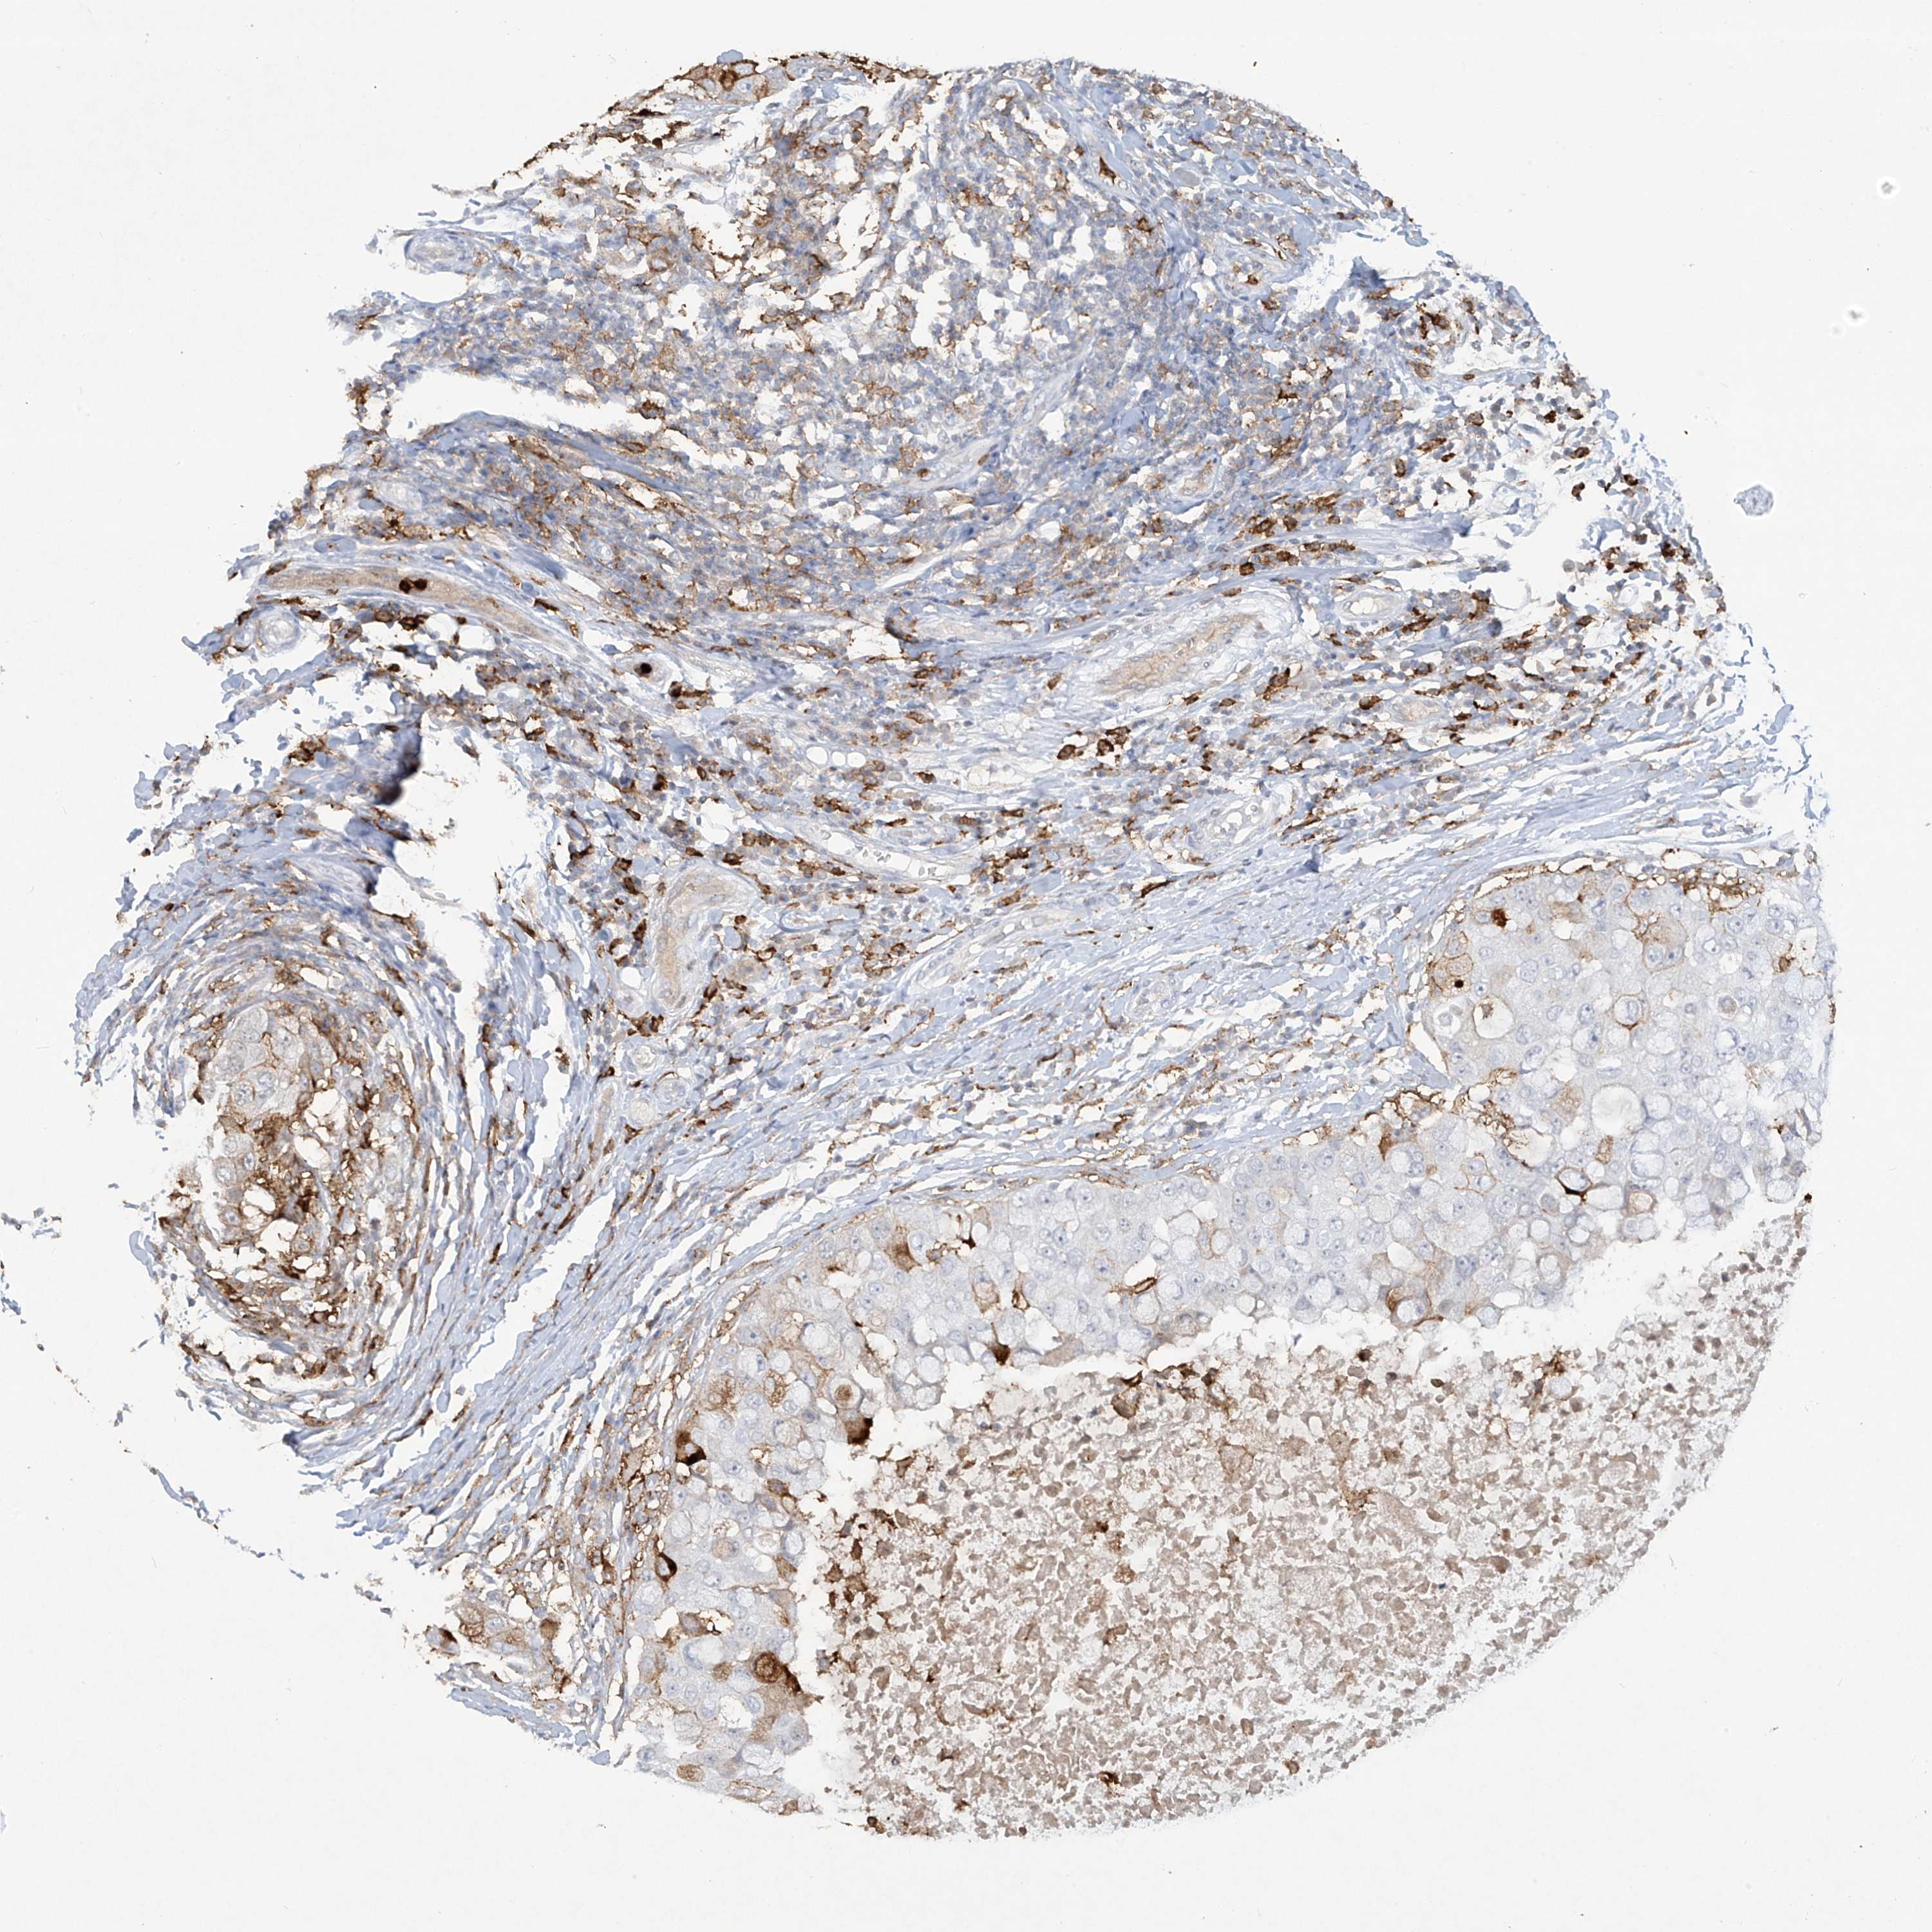

BRCA TCGA BRCA VALIDATION PROTEIN EXPRESSION

ANTIBODIES

AND

VALIDATION